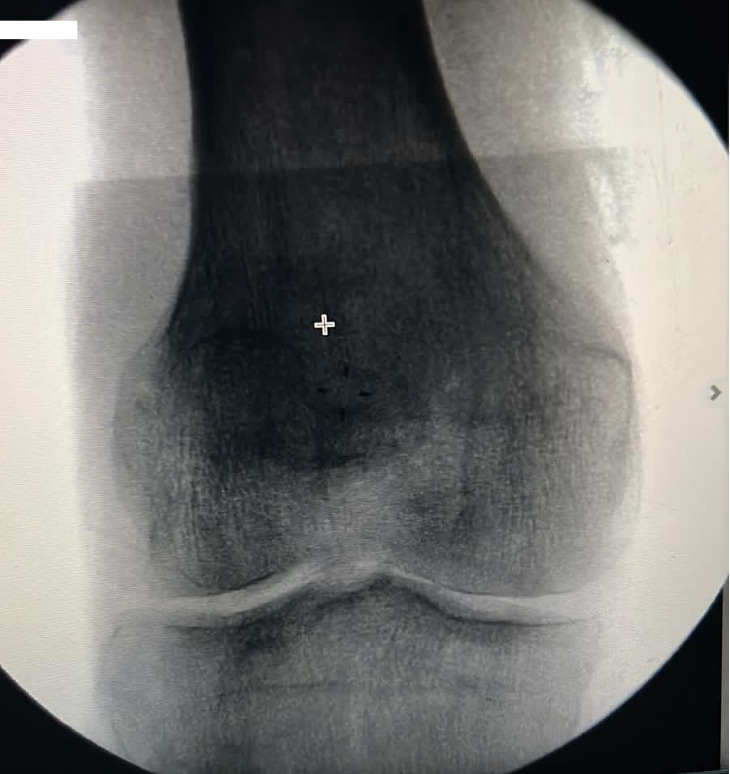

The patient was identified in the preop holding area. The right lower extremity was marked. He was then wheeled to the operating room whereby general endotracheal anesthesia was given in the supine position. All bony prominences were padded. A tourniquet was applied to the right lower extremity. Preoperative antibiotics were given. Time-out was done by staff. The tourniquet was inflated to 275 mmHg. The previous incision over the anterior knee was re-explored and extended mainly proximally. Both medial and lateral flaps were elevated. The previous distal patella sutures were removed. There was a small patellar tendon remnant distally, close to the tibial tuberosity. The avulsed distal patellar fragment was small and was excised. There was no possibility of primary repair without the use of an allograft due to the significant proximal migration of the patella. A quadriceps plasty was necessary. A V en Y quadriceps-plasty was performed and repaired using non absorbable sutures providing around 4 cm of distal migration of the patella. A tibialis anterior allograft was prepared and was whipstitched on both ends using non absorbable sutures. A 7 mm drill hole was made in the tibia slightly distal to the tibial tuberosity, the allograft tendon was passed in the hole and both ends were repaired to the patellar tendon remnant. Two 7mm interference screws were secured on each side of the tibia transverse tunnel to provide additional fixation of the tendon in the bone and to prevent any cutout. Krackow sutures were performed over the tibialis anterior tendon including the patellar tendon remnant and then both ends of the allograft converted to the distal patellar pole with a side to side repair done to centralize the repair ending in robust suture anchors fixation at the distal patellar pole and were secured using 4.75 SwiveLock (Arthrex, Naples, FL) anchors forming a delta or triangular configuration. An Arthroflex (Arthrex, Naples, FL) graft was draped and sutured on top of the tendon to provide more biological healing. Subsequently on each side of the patella a 4.5mm FT suture anchor (Arthrex, Naples, FL) was secured to reapproximate the medial and the lateral retinacula. An additional drill hole was made in the proximal patella in a transverse fashion and a fiber tape was passed and was secured in a Box and X configuration along with the sutures from the corkscrew anchors to the tibial tuberosity using 2 x 4.75 mm SwiveLock (Arthrex, Naples, FL) anchors in 30° of flexion as an added security construct to protect the Delta repair. Intra-op X-rays are shown in Figure 3. At this time extensive irrigation was done followed by release of the tourniquet and hemostasis. Closure was done using 1.0 Vicryl for the quadriceps followed by 2.0 Vicryl for the deep dermis and 3.0 nylon for the skin. Sterile dressing was applied followed by a knee immobilizer. The patient tolerated the procedure well. He was extubated successfully and wheeled to the recovery room in good condition.